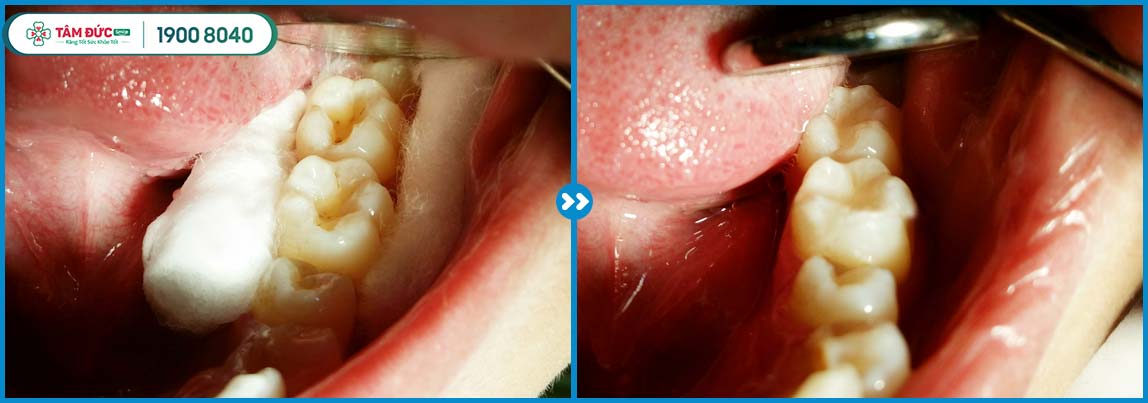

- Sử dụng vật liệu Composite hảng 3M tốt nhất của Mỹ để trám răng. Đảm bảo miếng trám bóng, trắng sáng như răng thật, bám dính vào men răng tốt và lâu xuống màu.

- Ứng dụng công nghệ trám răng Laser Tech vào liệu trình trám răng giúp miếng trám bám dính, tự nhiên.

Khách hàng trám răng thẩm mỹ tại nha khoa Tâm Đức Smile

Mỗi một nụ cười hài lòng của bệnh nhân chính là thước đo giá trị chân thực nhất về chất lượng điều trị, dịch vụ tại Tâm Đức Smile. Đừng e ngại, hoặc chần chừ việc trám răng. Đặc biệt là răng sâu, viêm tủy… càng kéo dài thời gian càng khó bảo tồn răng thật sau này.